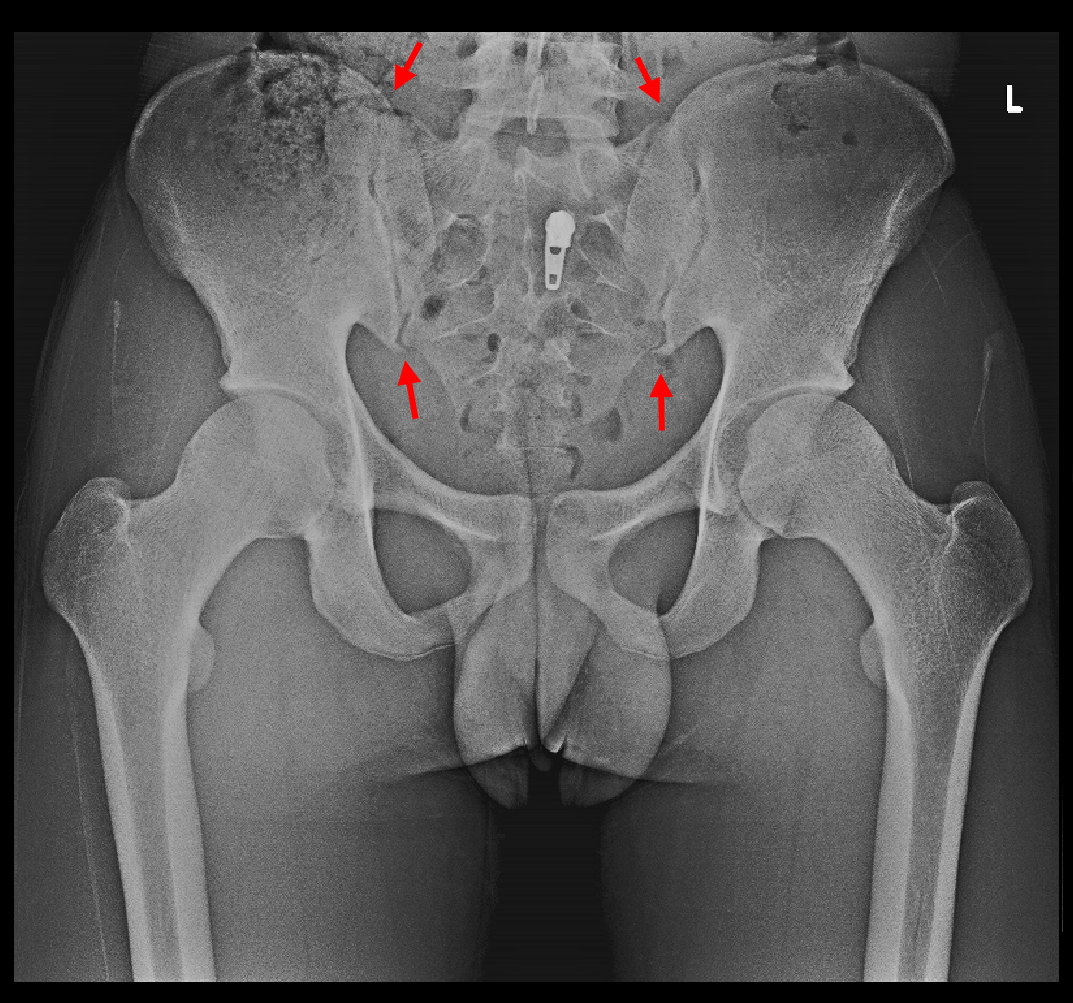

16才男Xp1.jpgS君の場合、レントゲン像で軽微なのですが、異常が確認されます。整形外科でFAIと呼ばれる所見です。FAIとはfemoral acetabular impingementの略で、日本語では大腿骨寛骨臼インピンジメント(インピンジメント=衝突)となります。右側の側面像では赤矢印の部分で大腿骨の骨頭部がわずかに肥厚しています。

S君の股関節レ線像と正常男性の股関節レ線像を比較すると、微妙ですが大腿骨頭部の外側部分が少し盛り上がっています。これがFAIの原因となります。大腿骨骨頭の外側部が盛り上がっていると、股関節を屈曲していった時にその膨隆部が臼蓋の周囲の関節唇を圧迫して損傷することになるのです。